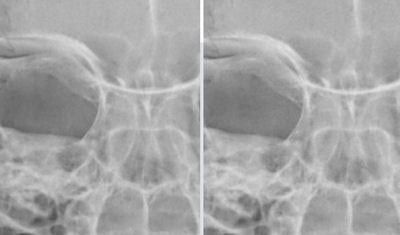

| Images depict zoom of skull phantom with 100% radiation dose (80 kV, 16 mAs) without RAYduce processing (left) and same phantom with 50% radiation dose (80 kV, 8 mAs) after RAYduce reconstruction. Images courtesy of RAYduce. |

RAYduce's technology attacks two types of noise in DR images: Poisson noise and Gaussian noise, which are inherent in all medical images. The algorithm processes raw DR data using compressive sensing theory and iterative reconstruction, producing images that are of higher image quality than those processed with existing DR algorithms, the company claims.

In addition to better image quality, RAYduce also enables radiologists to operate DR equipment with up to 60% less dose, Laupper said. While recent concerns over radiation dose have focused more on CT than radiography due to that modality's higher radiation burden, any reduction in dose is a good thing.

"The goal is always to reduce dose to as little dose as possible and still get diagnostic imaging," Laupper said. "The problem in the past was that by reducing dose you increased noise, and by increasing noise the images were not diagnostic anymore. With this method, you can reduce the radiation dose 50% to 70% without an increase in noise."